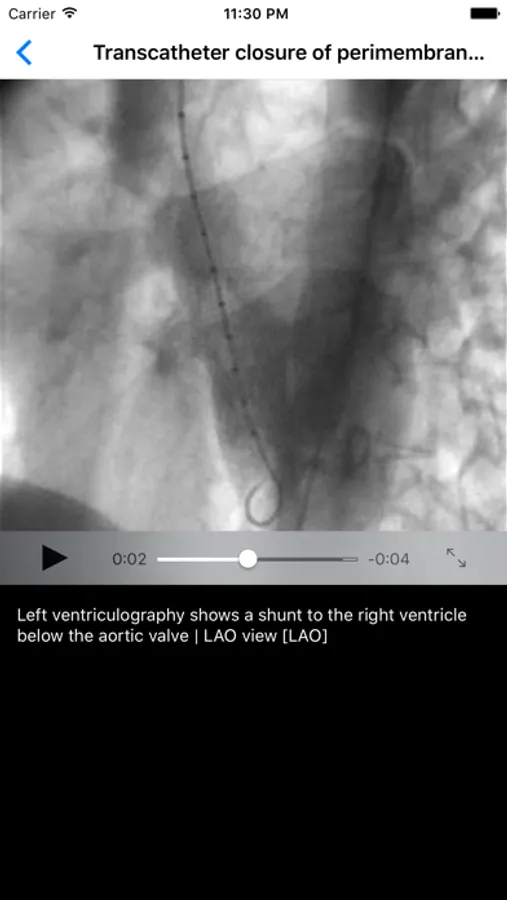

- Lite version of this education tool has limited number of excellent quality angiograms and other annotated images and videos